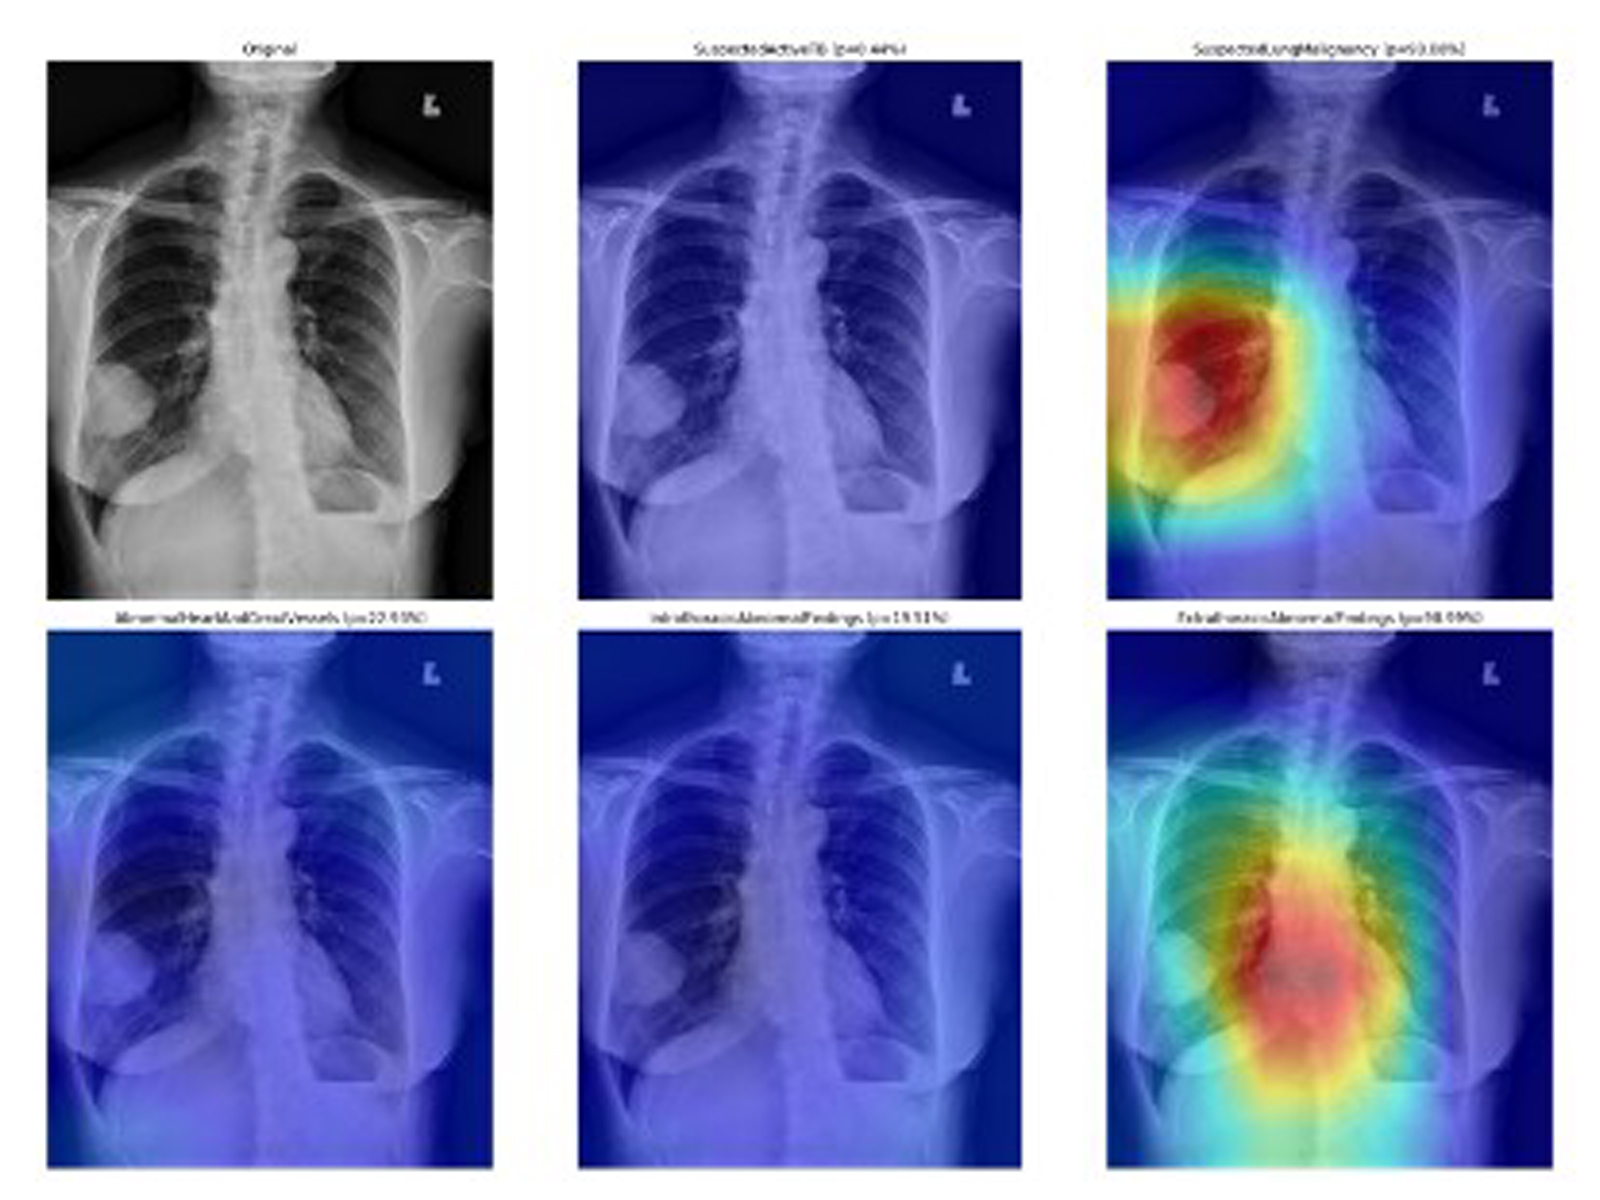

Doctors can then upload chest X-rays to the AI Chest 4 All system, which puts the X-ray into one of six categories: normal; suspected active tuberculosis; suspected lung malignancy or cancer; heart abnormality; intrathoracic abnormalities, such as Covid-19 or pneumonia; and abnormalities outside of the thorax, such as a bone or spinal cord abnormality.

The researchers found that their model achieved over 92 per cent accuracy in detecting heart disease, lung cancer and tuberculosis. “Since its launch in December 2021, the web-based system has been made available free of charge and adopted by more than 300 hospitals across Thailand,” says Tantibundhit.